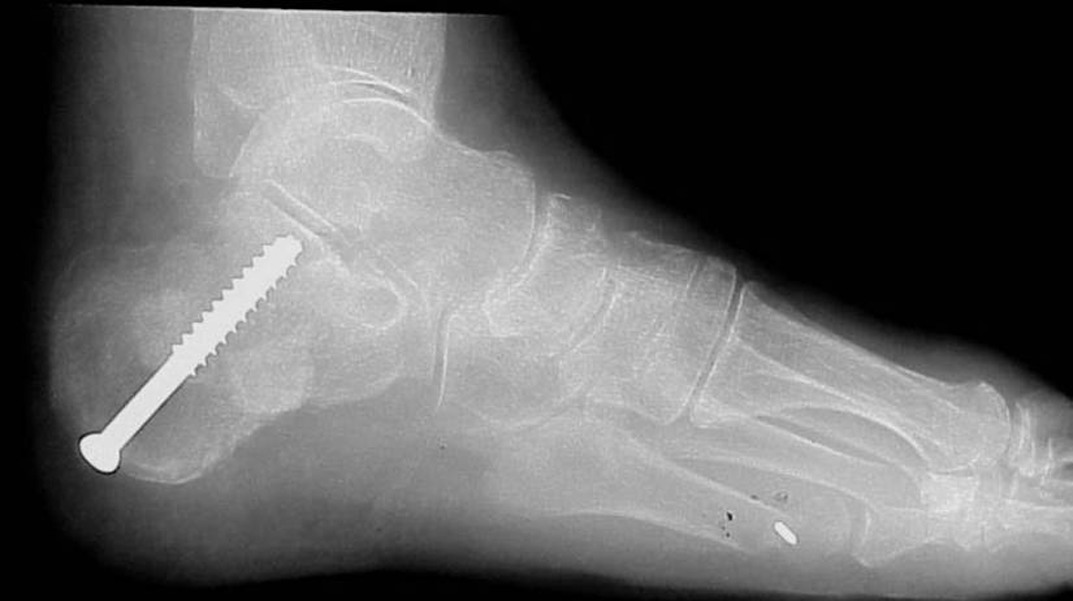

There are many surgical techniques for the treatment of tibialis posterior dysfunction due to an unstable subtalar joint. We prefer combining osseous and soft tissue procedures to correct the problem. Over the last six years, we have utilized the calcaneal Scarf to correct the rearfoot/subtalar position. The calcaneal Scarf allows accurate medial translation of the calcaneus while lengthening it in one osteotomy. The orientation of the osteotomy has increased stability over other calcaneal osteotomy options, allowing for ease of fixation and an earlier return to weightbearing. One benefit of this procedure is that it positions the subtalar joint from a valgus position into a more rectus alignment, thus reducing instability of the subtalar joint. This procedure also facilitates correction of transverse plane deformities. In the instance of severe instability that is not completely reduced by the calcaneal Scarf, we will augment our correction with an absorbable arthroereisis to further stabilize subtalar joint motion. & Correcting the weakened or absent tibialis posterior tendon is another crucial element to successful surgical outcomes. Podiatric surgeons commonly utilize a tendon transfer (flexor digitorum longus) or a tenodesis with the Cobb procedure (tibialis anterior). We prefer the Cobb procedure. However, in scenarios when one can avoid performing a tendon transfer, it is our preference to utilize the OrthoAdapt collagen scaffold (Pegasus Biologics). This material allows for reconstruction of the tibialis posterior tendon without sacrifice or insult to another tendon. With its cross-linked nature, the Orthoadapt is strong enough to maintain the correction. Its inherent collagen matrix also allows tissue in-growth, which ultimately will transition into normal host tendon tissue. In the most severe and longstanding cases of subtalar joint instability, arthritis of the subtalar joint may result. When bracing techniques fail in these situations, joint destructive procedures become an alternative. Studies have shown that surgeons can reduce 70 percent of subtalar joint motion by fusing the talonavicular joint. However, we prefer directly addressing the subtalar joint via an arthrodesis. & Arthrodesis of the subtalar joint will allow complete stability of the subtalar component of the rearfoot complex and positioning of the subtalar joint in optimal alignment. While fusion is never the preferred approach to any joint, it becomes necessary in many cases and can often lead to superior outcomes.